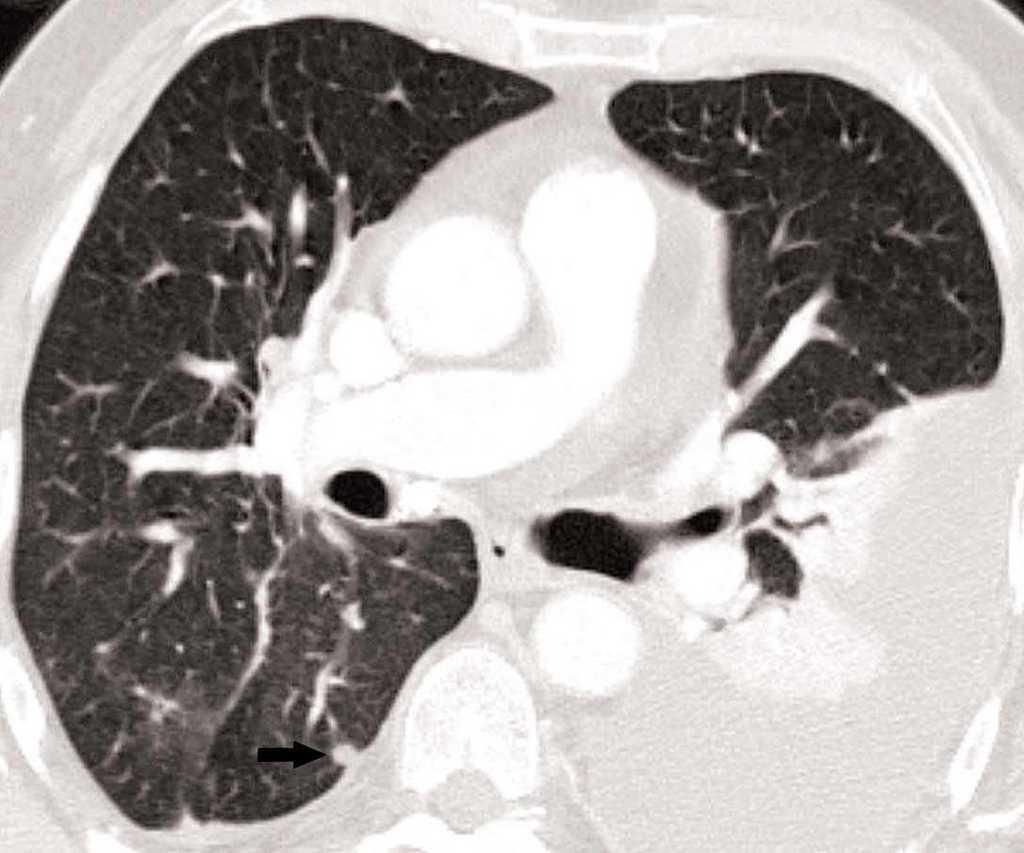

Metástasis pulmonares

La detección de nódulos pulmonares diferentes del tumor primario es muy superior cuando el estudio está hecho con un equipo de TCMD, debido al menor espesor de corte e intervalo de reconstrucción, lo que confiere una mayor resolución espacial. Esto permite hacer reconstrucciones de proyección de máxima intensidad (MIP) que incrementan significativamente la detección de nódulos, fundamentalmente los de localización central (fig. 13)18.

Fig. 13.--Metástasis pulmonares. (A) Atelectasia del lóbulo inferior izquierdo secundaria a tumor central con nódulo pulmonar contralateral (flecha). (B) Proyección de máxima intensidad (MIP) de 15 mm al mismo nivel que muestra más nódulos (flechas).